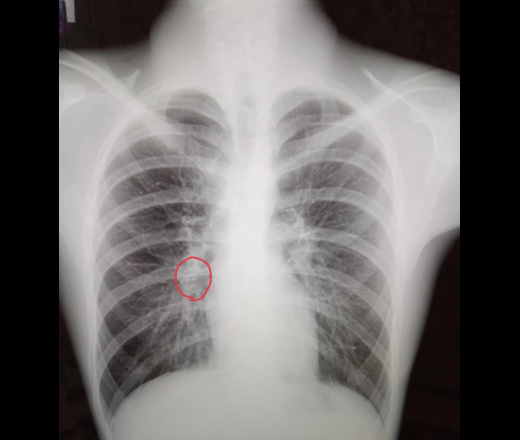

Рентгенологические изображения и синдромы патологии легких

Раздел: Кадры-подсказки